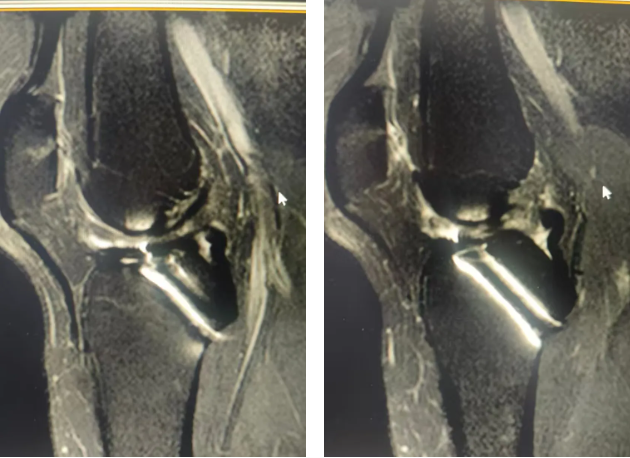

术前膝关节MRI检查

45岁的朱女士被膝盖不稳折磨了15年,近两个月更是频繁出现关节交锁。当多家医院因内固定取出难度高而拒绝手术时,朱女士经多方打听来到郑州大学五附院骨科一病区,找到徐明杰主任就医。徐明杰主任与张鹏飞医师为其查体后发现患者抽屉试验阳性,考虑患者膝关节不适不仅和内固定有关,而且可能和交叉韧带损伤有关,复查MRI检查后果然发现前交叉韧带断裂。